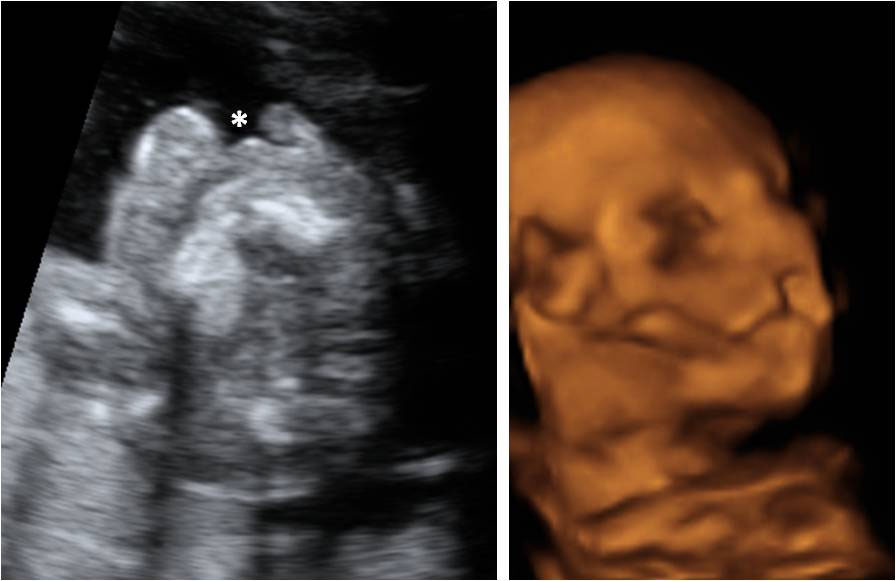

Ecografía Embarazo 4D Semana 20 - MALFORMACIONES FETALES